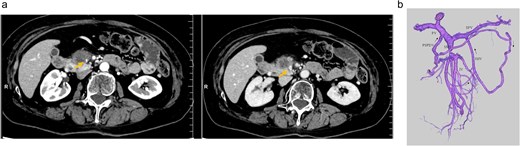

An elderly woman in her 80s presented to our hospital with prolonged epigastric pain. She was diagnosed with pancreatic cancer (PC) in the uncinate process, with severe stenosis of the SMV (Fig. 1a, left). She had previously undergone laparoscopic right hemicolectomy for cecal cancer 6 years earlier. The PC was considered borderline resectable without lymphadenopathy or evidence of distant metastasis, and she received three cycles of NAC with gemcitabine plus nab-paclitaxel (GnP). Although the SMV stenosis showed mild improvement after NAC (Fig. 1a, right), preoperative 3D imaging revealed that the jejunal veins drained separately and that prominent collateral pathways bypassing the SMV–PV axis had developed (Fig. 1b). We obtained fully informed consent, particularly regarding the potential procurement of a VG from her neck, and a pancreaticoduodenectomy was planned, preserving the collateral venous pathways and without SMV reconstruction.

(a) Preoperative contrast-enhanced CT in the portal venous phase demonstrated a hypovascular tumor measuring 20 mm in the pancreatic uncinate process and mild improvement in SMV narrowing (arrow, pre-NAC in left image, post-NAC in right image). (b) Preoperative 3D imaging demonstrated that the jejunal veins were discontinued separately, and there are three collateral pathways, via posterior superior pancreaticoduodenal vein, inferior mesenteric vein through the right gastroepiploic vein, and stenotic SMV with intramesenteric anastomoses. SMV: Superior mesenteric vein, NAC: Neoadjuvant chemotherapy.